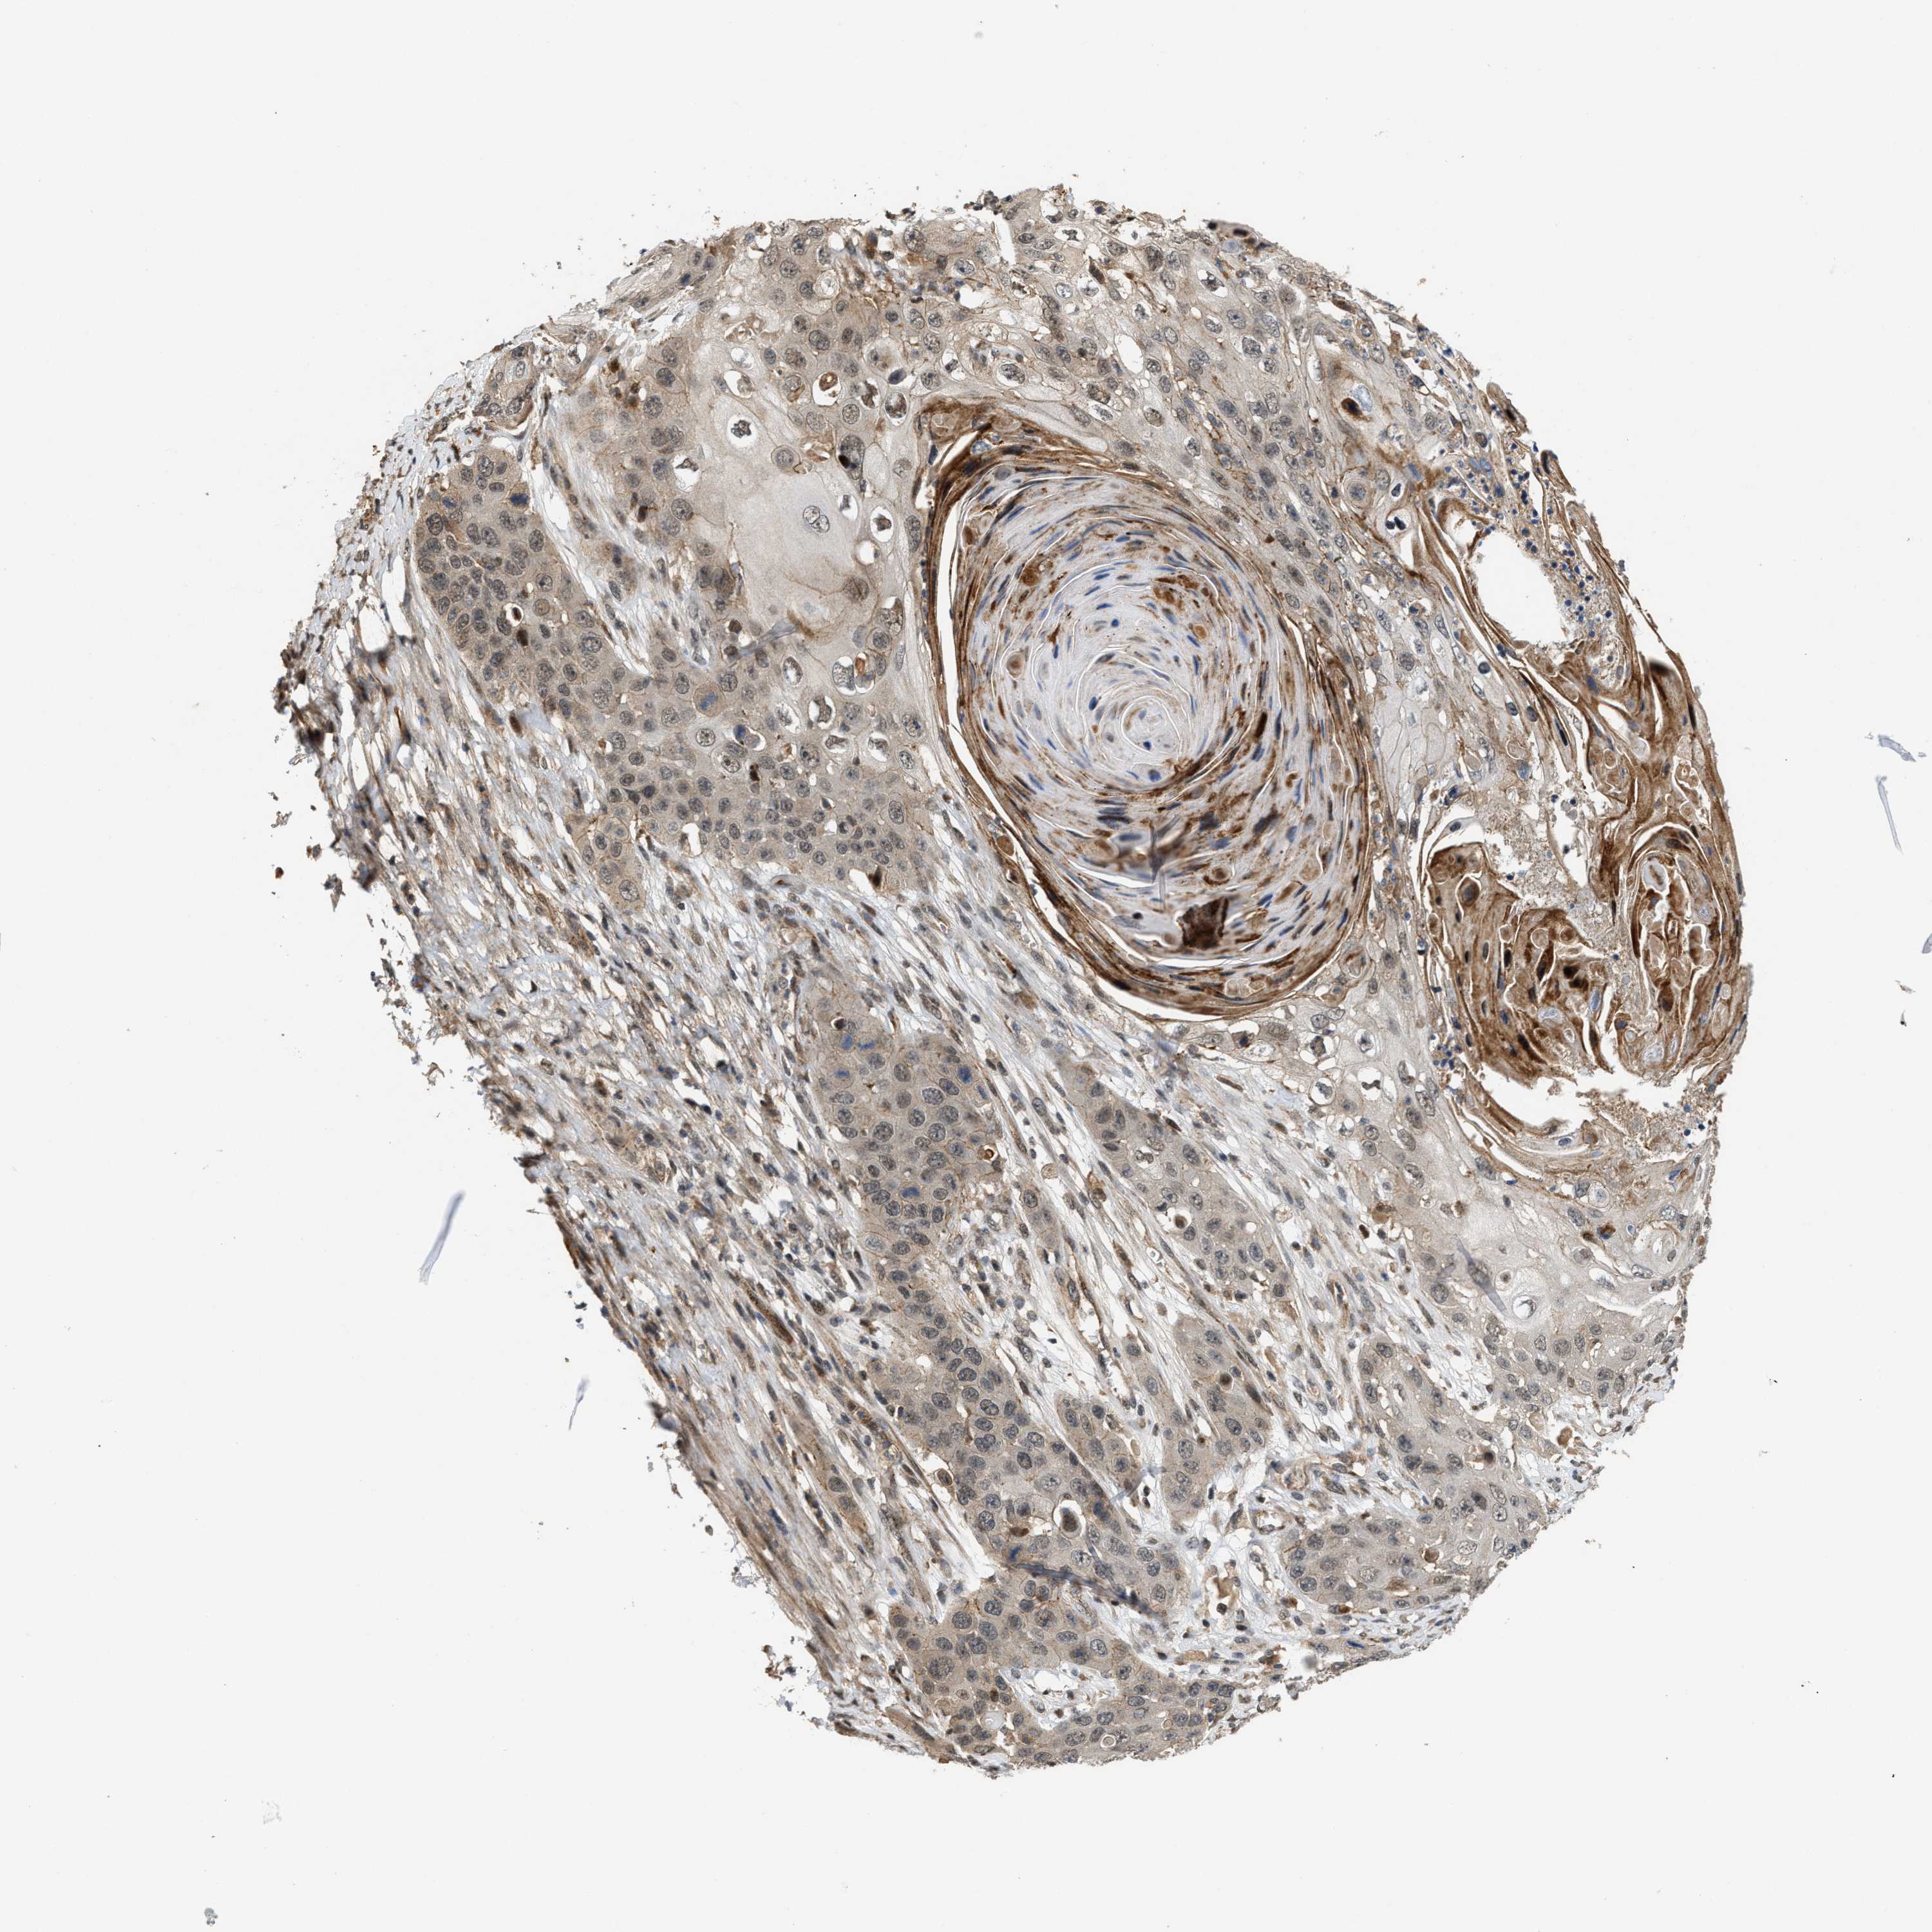

Basal cell and squamous cell cancer

SKIN CANCER - Protein expressioni

A mouse-over function shows sample information and annotation data. Click on an image to view it in a full screen mode. Samples can be filtered based on level of antibody staining by selecting one or several of the following categories: high, medium, low and not detected. The assay and annotation is described here.

Each image is clickable and will lead to virtual microscopy that enables deeper exploration of all samples and also displays staining intensity scores, fraction scores and subcellular localization as well as patient and tissue information for each sample.

Antibody HPA020880

Staining

High

Intensity

Strong

Quantity

>75%

Location

Nuclear

Basal cell carcinoma